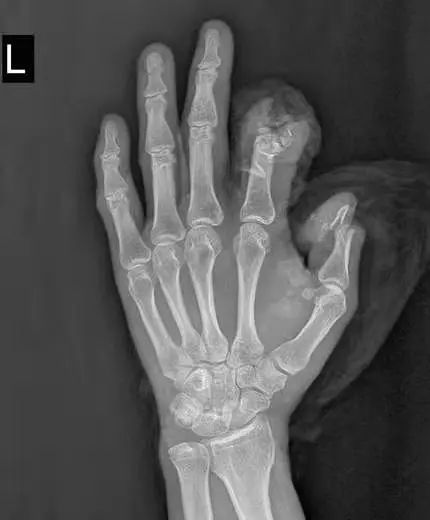

医院手足显微外科接诊,拍摄X片显示:左拇指近节远端指骨、指间关节及末节指骨大部分缺损;左食指近节远端以远指骨缺损。完善相关检查后,立即准备手术。

术前、术中照